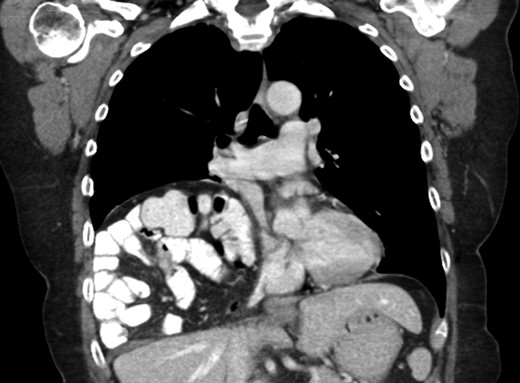

A 69-year-old female was referred to our clinic for an incidental finding of a large Morgagni hernia found on a recent CT chest scan for lung cancer screening. Patient reported occasional shortness of breath after prolonged ambulation but denied chest pain. She did have remote history of acid reflux symptoms but nothing recently. She denied issues with prematurity or issues with development as an infant, chest trauma, or MVA history. She did complain of occasional right shoulder pain but attributed this to arthritis. Denied history of heart attack, stroke, DVT, or PE. She had a 30-pack-year smoking history but quit a year prior. She was up-to-date on her colonoscopy, current within the past year. She denied hematochezia and melena, bowel habit changes or major body weight changes as well as any current abdominal pain. On examination her vitals were within normal parameters. Heart and lungs were unremarkable. Abdominal examination was soft with normal bowel sounds and nontender. Remainder of examination was unremarkable. Laboratory values included a normal CBC and BMP. A CT chest scan had demonstrated a large retroxyphoid hernia of Morgagni involving several loops of small bowel and transverse colon located in the right inferior hemithorax (Figs 1 and 2). No evidence of acute incarceration or strangulation were noted. A detailed discussion was undertaken with the patient regarding her hernia and she was consented for a laparoscopic repair with mesh.

Another slice of the CT scan of the chest revealing the large size of this Morgagni hernia with multiple loops of small bowel and colon in the right inferior hemithorax.